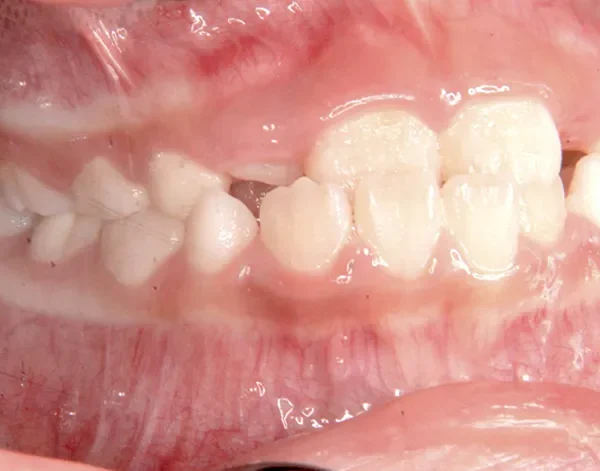

初診時年齢 小学校1年生 (女性) 主訴 受け口

診断名 叢生・反対咬合 装置名

状態 永久歯が生える隙間がない(叢生)

受け口(下顎前突/反対咬合)

下顎が大きい傾向があります。

上下の真ん中にズレがあるのと、上下とも永久歯の生えるスペースがせまいため、オリジナル矯正装置でスペースを作り、受け口も改善していきます。